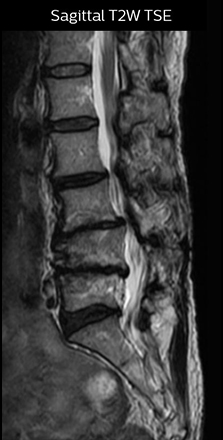

At Northern Fukushima Medical Center in Japan, excellent MRI visualization of nerves helps support confident diagnoses and informs surgical treatment decisions for patients with lower limb symptoms. MRI technologist Tanji and orthopedic surgeon Dr. Yabuki share how direct nerve visualization with the 3D NerveVIEW method adds information when diagnosing atypical herniations. The additional insights changed their way of working and benefit their patient care, as illustrated by some clinical examples.

“In patients with lower extremity neurological symptoms, NerveVIEW helps us to determine the disease matching the patient’s symptoms by directly visualizing the nerves. We use the sequence mainly, when there is suspicion of intraforaminal stenosis, extraforaminal stenosis or lateral disc herniation, which is often based on routine T2- and T1-weighted images. Additionally, the excellent depiction of the course of nerves makes NerveVIEW a good navigator when applying treatment such as block therapy or surgery.”

The key concept in MR neurography, Dr. Yabuki stresses, is the ability to directly visualize spinal nerves, versus inferring the presence of pathology indirectly. “Before NerveVIEW, we estimated compression of the nerve by looking for the presence or absence of fat signal on other MR images,” he says.

“For example, in sagittal images, when the presence of fat is observed in the intervertebral foramen, it suggests that there is a margin around the nerve. Similarly, the absence of fat indicates that the nerve is being compressed. So, we used to deduce nerve compression indirectly. With NerveVIEW, however, we can observe the condition of the nerves directly, regardless of the presence or absence of fat. We always prefer such direct observation of anatomy over having to make an inference about it.”

“Although symptoms of typical disc herniation and atypical hernia are very similar, the actual site of herniation is different. It is therefore important to characterize the nerve’s condition both inside and outside of the intervertebral foramina. “Conversely, if we see no abnormality in NerveVIEW, we can assume at least that there is no severe condition that requires surgery. Like this, it can help us avoid unnecessary surgery. NerveVIEW can have a tremendous impact in this way.”

“NerveVIEW is really useful for those cases where a nerve disorder is strongly suspected based on the clinical examination but our regular MRI images do not show any findings. These atypical herniations and spinal canal stenosis, occurring in 5% to 15% of the total lumbar herniation/stenosis cases are our main target when using NerveVIEW,” says Dr. Yabuki.